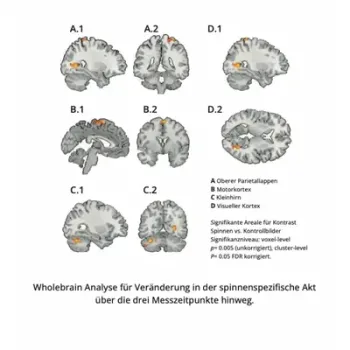

This effect increased in the second phase of the test and extended to 6 brain areas.

"After repeated use (Total 5 hours per personon average, spread over 4 weeks) of the Mind Switch® Fear & Phobia App, a strong reduction in the response to images of spiders was demonstrated in brain areas usually strongly associated with phobias: In the right amygdala, average activity was reduced by 117%, and in the left amygdala by an average of 145%. In the visual areas of the brain, there was a reduction from 8 units to an average of -1.6 units, in somatosensory-motor regions from 15.1 to - 2.8 units, in the parietal lobe from 8.6 to -5.3 units, and in the cerebellum from an average of 12.2 to 2.7 units. In summary, these results clearly indicate that in people suffering from phobias, a significant reduction in brain activity is observed with repeated use of the app. And this is in brain areas associated with anxiety."

Study results presented graphically

Whole brain analysis

Whole brain analysis